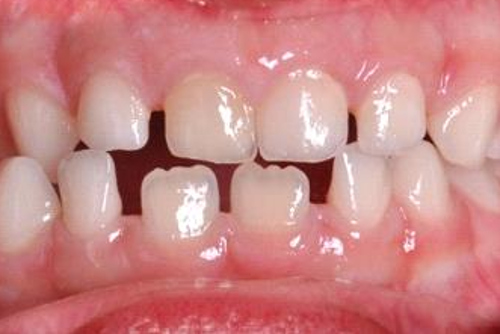

Прикусы, когда нужна ранняя коррекция, это — открытый прикус, перекрестный и обратный (мезиальный) прикус.